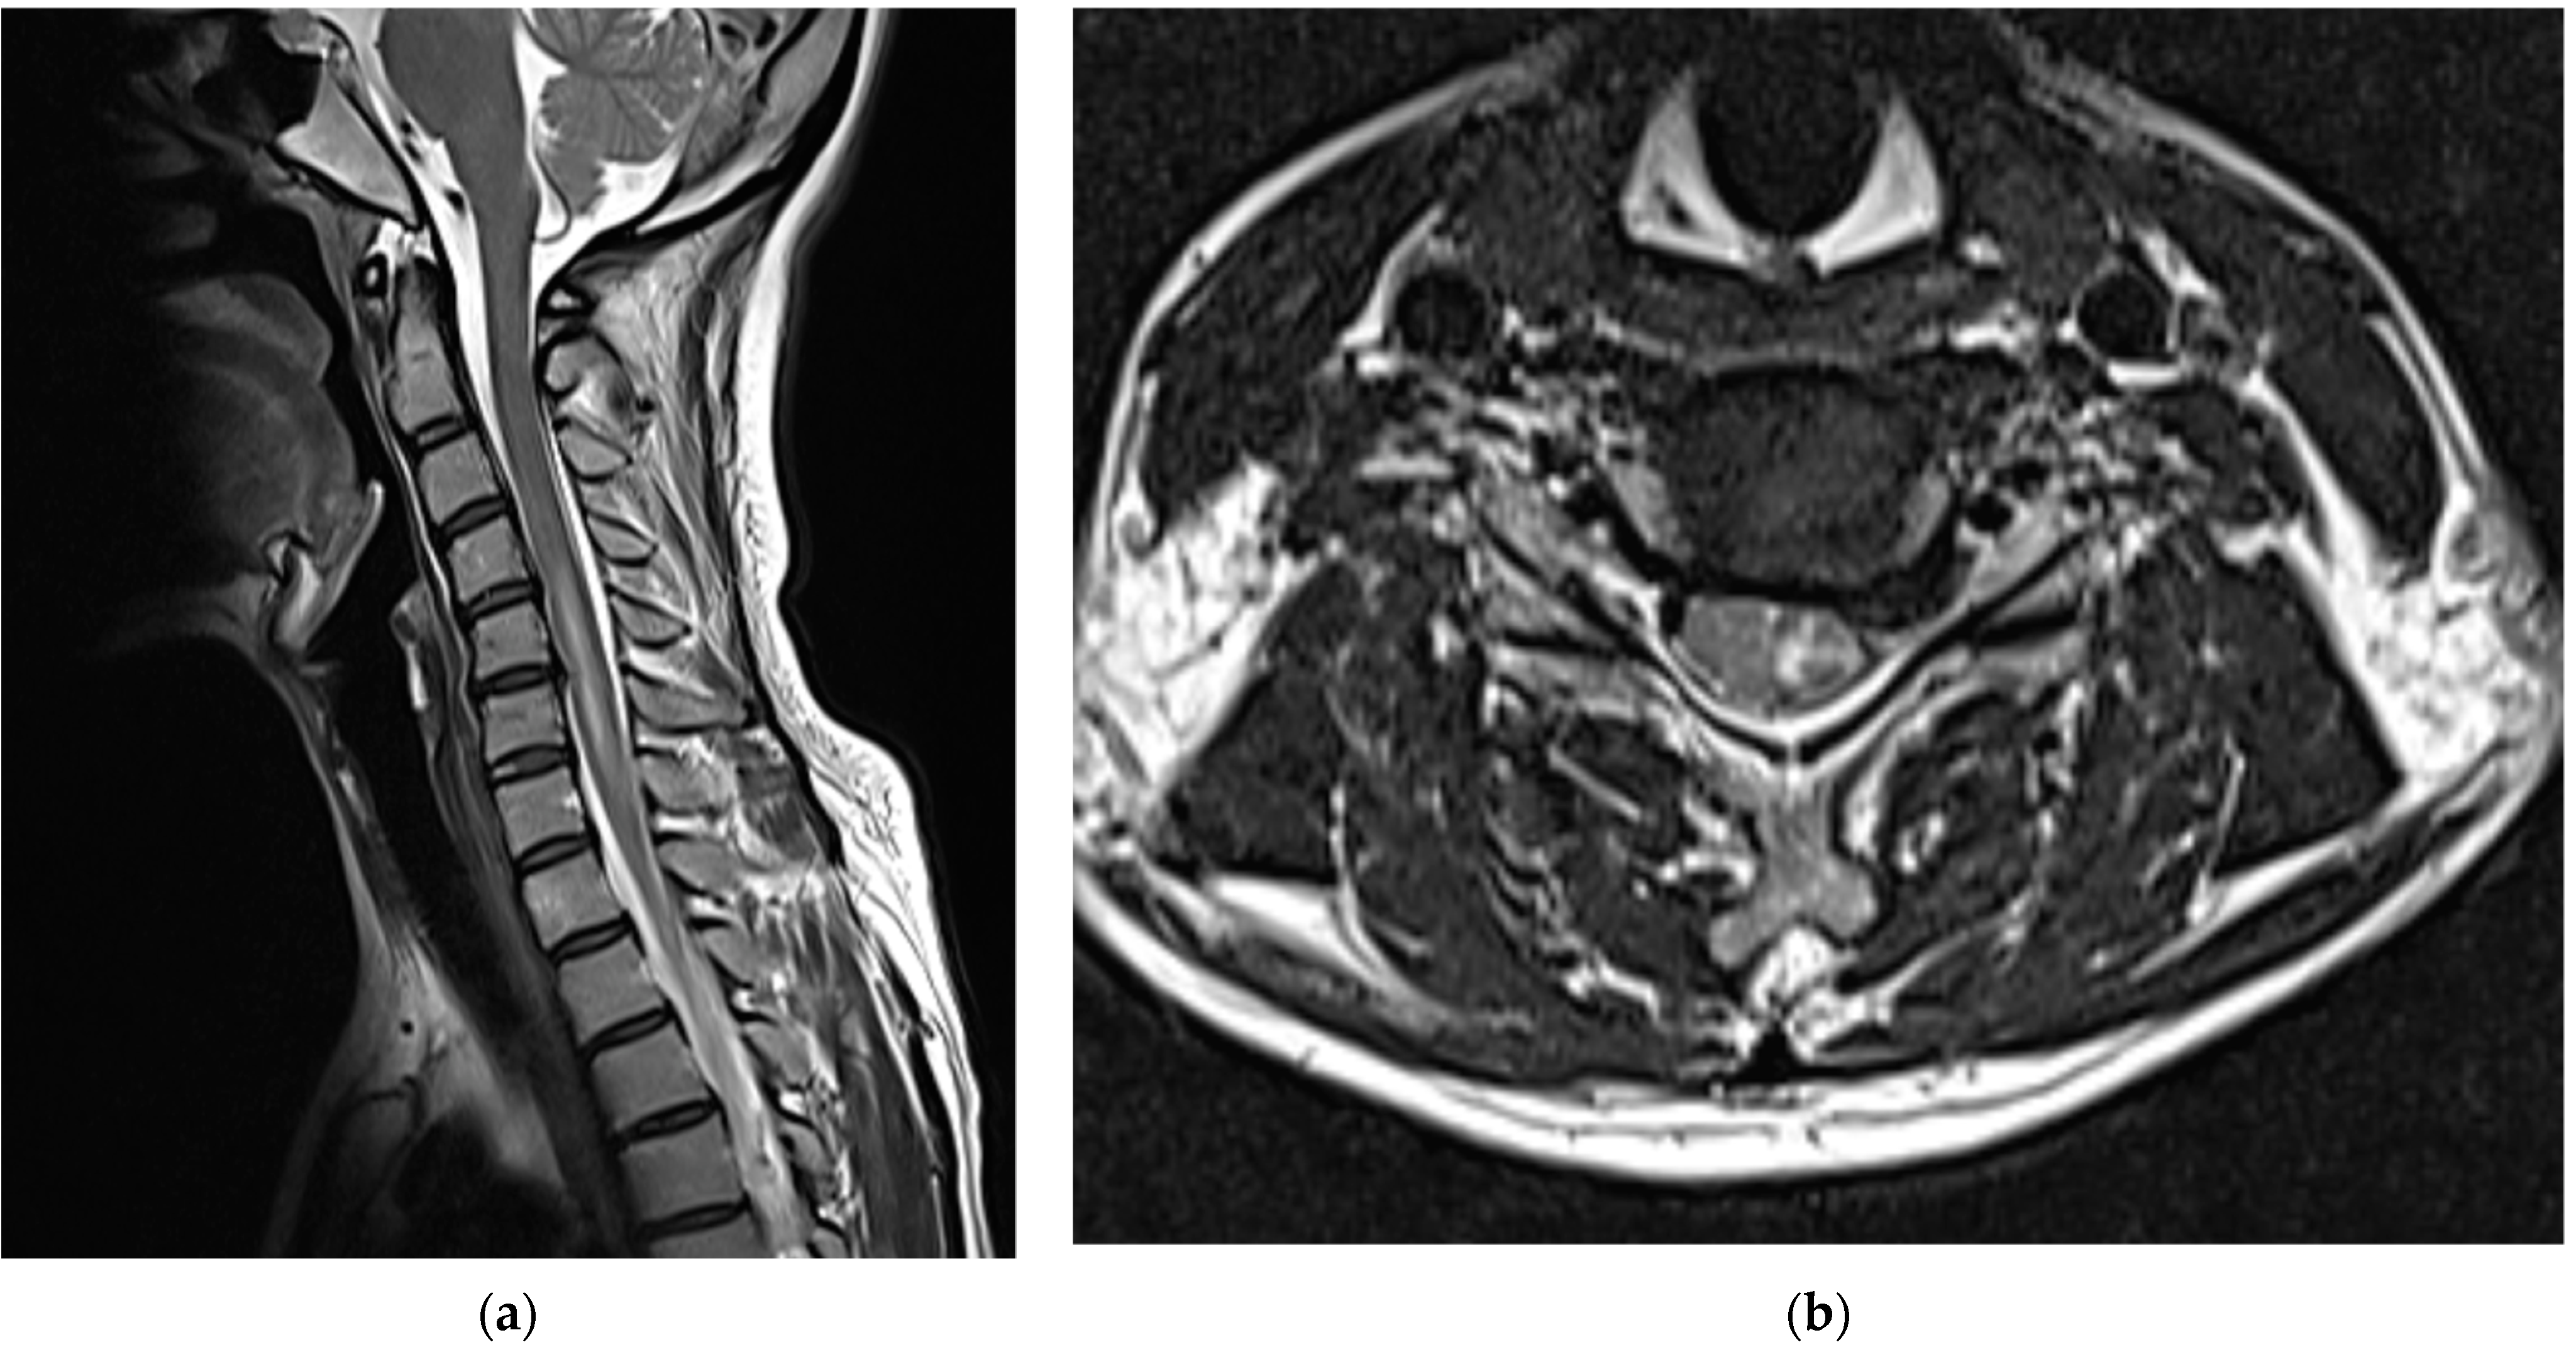

Medications, excluding steroids, were continued for 1 month after the procedure. The patient reported that their left upper arm motor weakness improved slightly (4/5); however, sensory changes persisted. Two months after the procedure, shoulder strength was almost fully restored (5/5), left-hand motor weakness slightly improved further (4/5), and sensory function had almost returned to normal; however, the patient complained of persistent paresthesia in her left hand. At 3 months after the procedure, her left-hand motor weakness showed almost complete recovery (5/5); however, abduction of her fifth finger diminished to 4/5, and the decreased sensation in the dorsum of the left hand persisted. Six months after the procedure, abduction of the fifth finger continued to decrease and sensory deterioration in the dorsum of the left hand remained. As detected during the follow-up MRI performed 6 months post-procedure, the T2 high signal intensity in the left central intramedullary region decreased compared to that observed previously; however, spinal cord swelling was still present, albeit reduced (Figure 4).

Figure 4.

Cervical spine magnetic resonance images obtained 6 months after the procedure: (a) T2-weighted sagittal image and (b) T2-weighted axial image of the C5/6 level. The extent of the left central intramedullary T2 high signal intensity (elongated lesion in the spinal cord) from the C4/5 to C7 levels slightly reduced. The spinal cord swelling is also reduced.

In addition, left C7/8 radiculopathy with acute denervation was confirmed by electromyography that was performed at 6 months after the procedure.